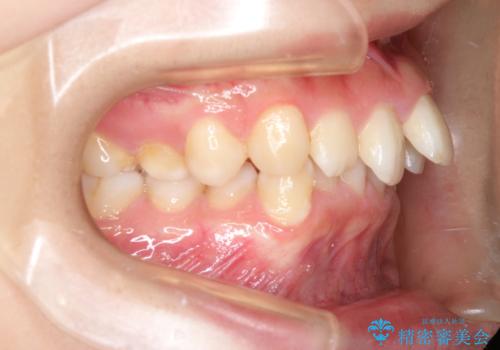

奥歯を後方に移動させるのと、歯と歯の間にわずかに隙間を作ることでスペースを確保して、抜歯をせず歯を並べる計画としました。

ガタガタの度合いが大きかったので少し時間がかかりましたが、非常に協力的な患者様でしたので、抜歯をせず計画通りに治療を終えることができました。